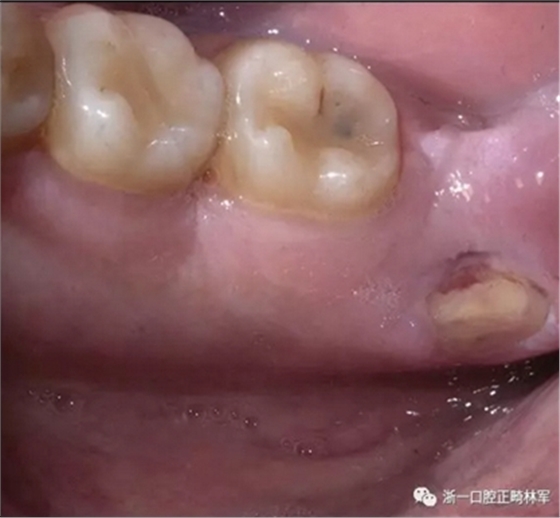

两天后,患者自述覆盖在下颌舌骨嵴的一块粘膜脱落,暴露了下方的骨质(图4),伴有疼痛和烧灼感,特别是与某些食物(面包,辛辣食物)相关。 因此,他被转诊到了荷兰阿姆斯特丹的学术医学中心的口腔颌面外科治疗舌侧下颌骨骨坏死。

图4. 右侧下颌舌骨嵴区域的舌侧下颌骨骨坏死